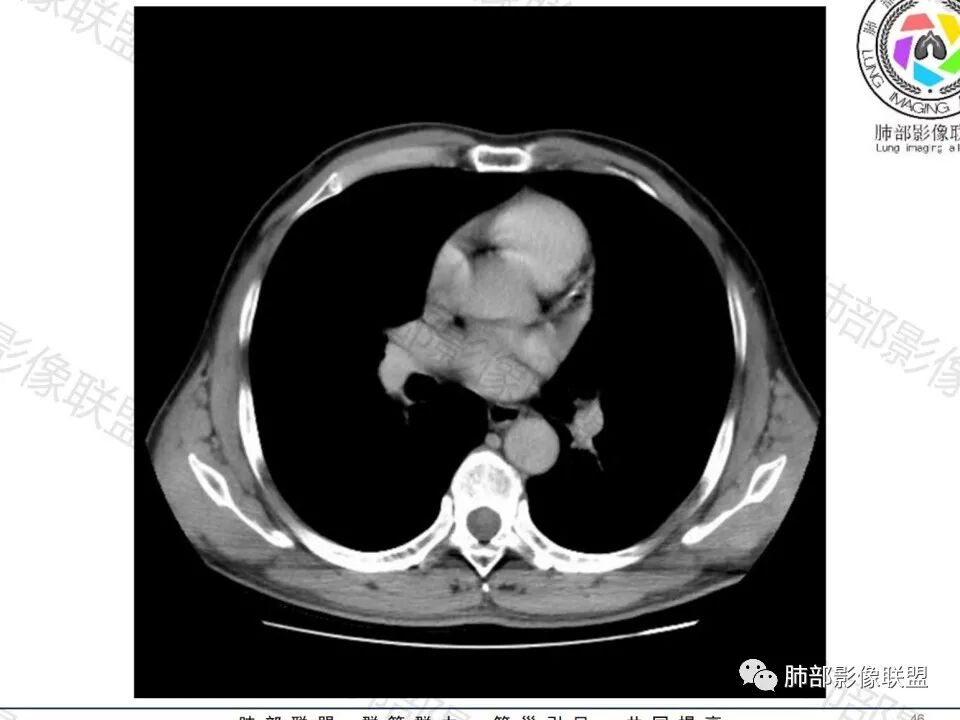

这枚结节的纵隔窗在没有调节窗位的情况下,已经很密实了,说明这个结节里面是软组织的成分,这与普通炎性结节(隐球菌等)的密度还是有区别的,很多年前就有人提出,纵隔窗显示越大,恶性可能越大;

结节周围有磨玻璃影,边界似清不清的,但是总体不如炎性晕征那么模糊;

有收缩力,但是很轻,按照常理,实性结节因为有占位效应,不太会有收缩力,但是叶间胸膜有凹陷。所以讲,这个结节还是开了放心。